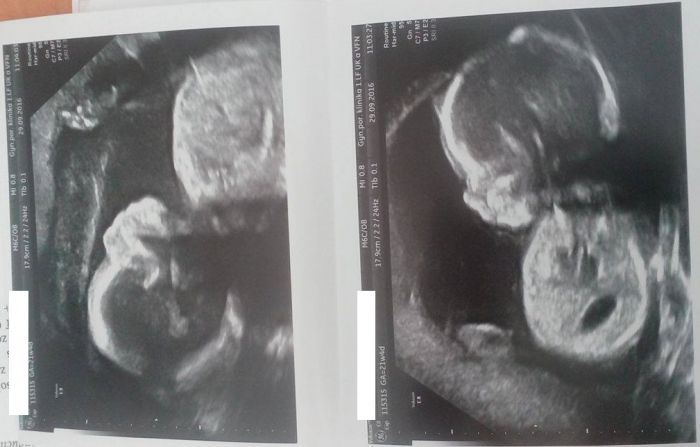

Autor: Elderflower 29.9.2016 v 13:42

Dneska jsem byla na větším ultrazvuku a dozvěděla jsem se, že Luke a Leia vypadají zdravě. Když jsem se zeptala, jestli to je kluk (něco se tam u jednoho podezřele houpalo), bylo mi sděleno, že jak to prý má vědět. Tak zatím nic nevím a budeme muset vymýšlet dvě a dvě jména. Ale jinak jsou tabulková, jenom ten jeden podezřelý chudinka je pořád v popředí zájmu kvůli pozitivnímu screeningu, má lehce šouplý jeden parametr hlavičky (ale ještě hluboko pod hranicí nějakého znepokojení), nicméně mě raději stejně posílají ještě na jeden podrobnější UTZ a moje doktorka mi napsala doporučení na kardio. Užiju si, no.

Ale jinak to nebylo moc příjemné, když vám někdo dloubne ultrazvuk bez varování pod žebra, brr... Je škoda, že Apolinář je velká nemocnice a není tam prostor pro trochu osobnější přístup, třeba ke své gynekoložce přijdu, sestřička mě jakousi magií okamžitě identifikuje, ví, jak se jmenuju, všechno mi vysvětlí... Takhle mám ve zprávě akorát napsáno, že nález se mnou byl konzultován v rámci ekukačního pohovoru, přičemž nějak zvlášť edukovaně si nepřipadám.